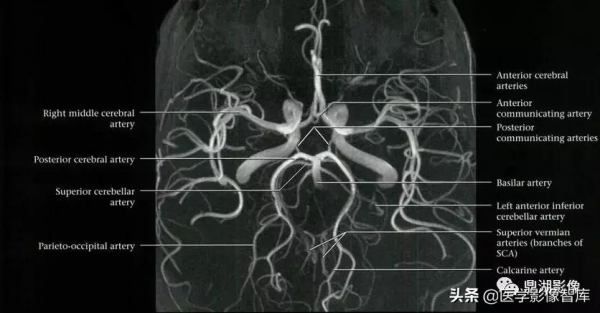

頸部及顱內血管

椎基底動脈系統及其分支解剖(前後位):

1.右椎動脈 2.左椎動脈 3.脊髓前動脈 4.小腦後下動脈(PICA)

5.基底動脈 6.小腦前下動脈(AICA) 7.腦橋外側支

8.小腦上動脈(SCA) 9.大腦後動脈 10.後交通動脈 11.頸內動脈

基底動脈(BA)

在腦橋前的正中溝內。正常管徑 3~4mm,平均長 32mm。左側椎動脈造影前後位:

大腦後動脈(PCA)

1. 基底動脈

2. 後交通動脈

3. PCA P1 段

4. 穿支

5. P2 段

6. 小腦上動脈

7. 基底動脈的腦橋支

8. 顳前動脈

9. 顳後動脈

PCA 分 4 段:P1 交通前段;P2 環池段;P3 四疊體段;P4 距裂段

PCA 分出 3 種類型分支:中央支、腦室及脈絡叢支及大腦支。